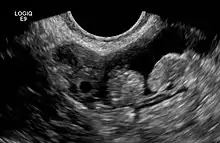

2 epiploic appendages next to an ovary in pelvic ultrasound

The epiploic appendices (or appendices epiploicae, or epiploic appendages, or appendix epiploica, or omental appendices) are small pouches of the peritoneum filled with fat and situated along the colon, but are absent in the rectum.